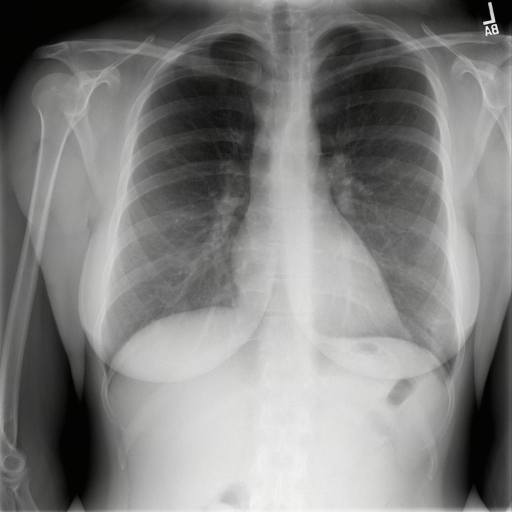

Public Dataset Integration for Breadth. We leverage established open-source datasets (e.g., MIMIC-CXR [28], CheXpert [24], and ROCO [47]) to provide a foundational layer of visual variety. These datasets offer a vast quantity of samples covering common pathologies and standard anatomical views. However, raw annotations in public datasets are often noisy or limited to binary classification tags (e.g., “Pneumonia: Positive”).

Stage 3: Multi-Granularity Instruction Formatting. To enable the model to handle various user intents, we do not simply pair the image with a single caption. Instead, we generate diverse instruction-response pairs derived from the generated caption. These include: (1) Descriptive Instructions (e.g. “Describe the findings in this chest X-ray.”), (2) Diagnostic Q&A (e.g. “Is there evidence of pleural effusion? If so, describe its location.”), (3) Localization Tasks (e.g. “Identify the region responsible for the patient’s shortness of breath.”), and (4) Reasoning Prompts (e.g. “Based on the visual evidence, what is the most likely diagnosis and what follow-up is recommended?”).

The training dataset is built mainly from radiology imaging data (e.g., X-rays, CT scans, MRI) and public de-identified radiology datasets, which include pathological/normal cases, metadata and expert annotations. Given the varying diagnostic complexity and tool utility of raw radiology data, a two-stage filtering pipeline is adopted to create an effective RL training set:

Medical report generation stresses long-form coherence and, more importantly, faithfulness: the ability to describe findings without introducing subtle hallucinations or unsupported claims. Evaluation in this category is particularly sensitive to protocol choices (e.g., what constitutes an omission versus an incorrect addition), which motivates our unified prompting, structured output requirements where applicable, and complementary inhouse faithfulness tests. Tab. 7 lists the report benchmarks included.